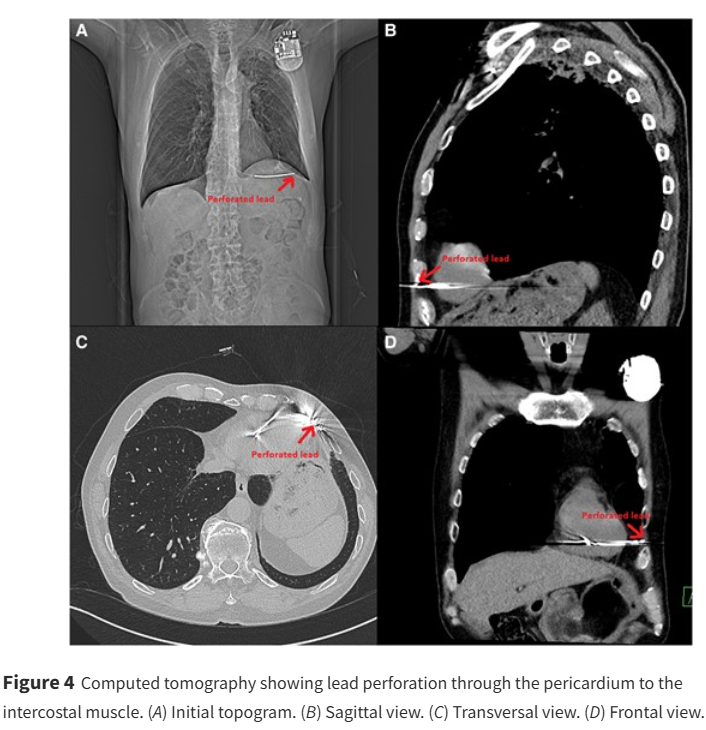

Spot diagnosis: What happened here & what would you do? ow.ly/LWiw50VOOYP #EHJCaseReports Philipp Sommer Tee Joo YEO Aaysha Cader Boldizsar Kovacs Erik Rafflenbeul A.Nazmi Calik Obayda Azizy Sara Moscatelli EHJCaseReports Editor-in-Chief #CardioX #echofirst